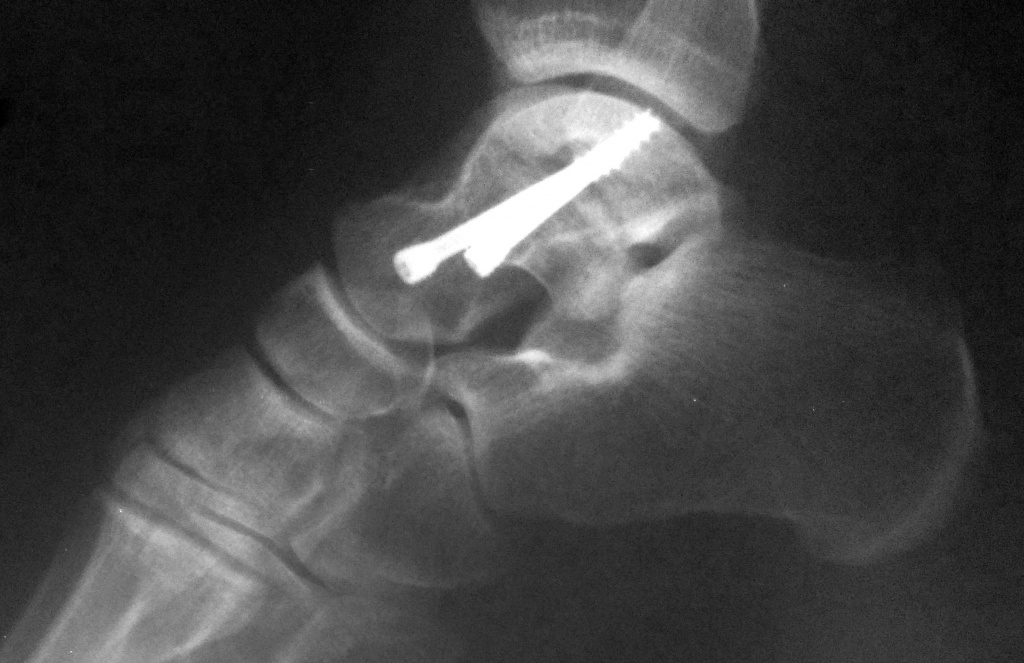

Рентгенограмма пациента с переломом таранной кости

Рентгенограмма после остеосинтеза винтами